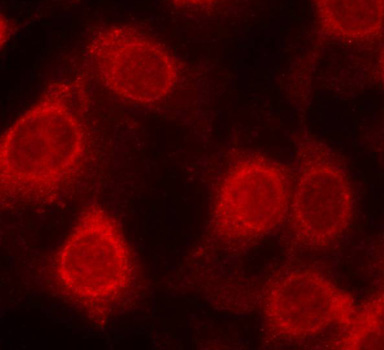

• AP0228: image 2

Immunohistochemical analysis of paraffin-embedded human breast carcinoma tissue using Phospho-EIF4E-S209 antibody.

Immunofluorescence staining of methanol-fixed MCF cells using Phospho-EIF4E-S209 antibody.